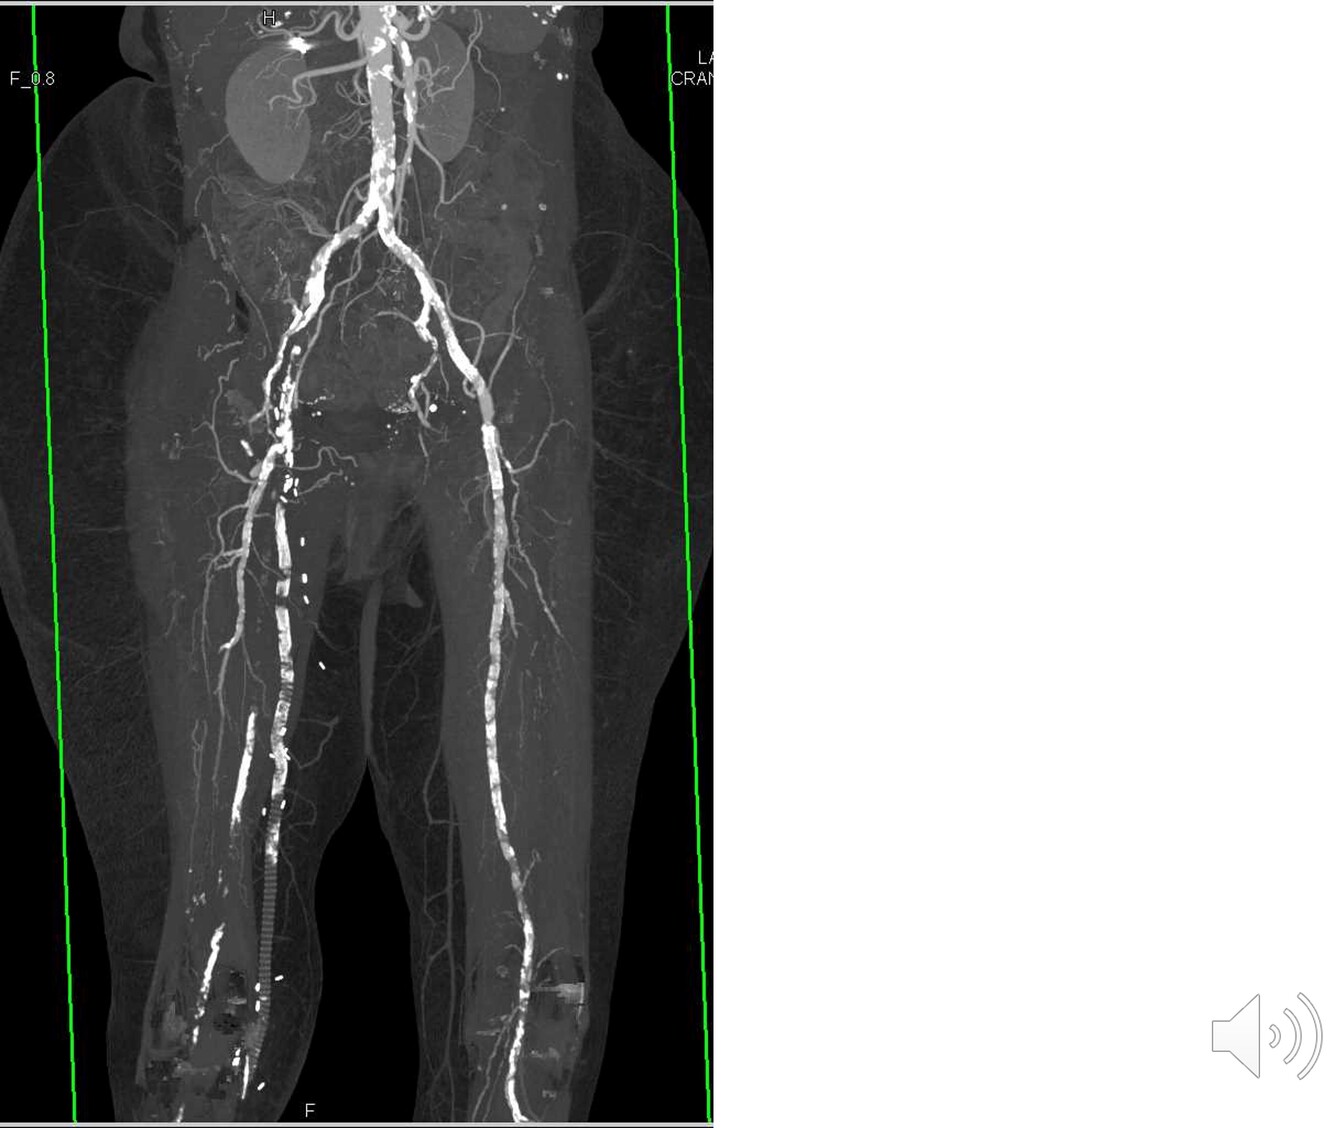

lower extremity vasculature

A

-at the inguinal ligament the external iliac becomes the common femoral artery

-superior, middle, inferior genicular arteries - collateral circulation

-anterior tibial -> dorsalis pedis

How well did you know this?

1

Not at all

2

3

4

5

Perfectly